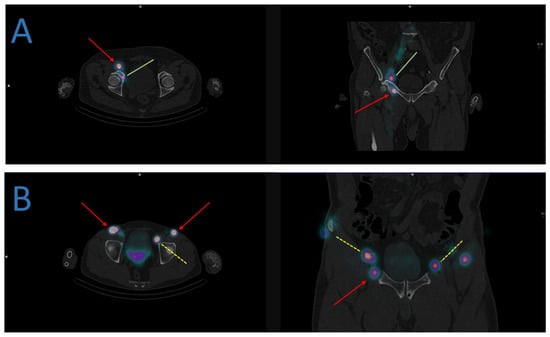

- Hinsenveld, F.J.; Wit, E.M.K.; van Leeuwen, P.J.; Brouwer, O.R.; Donswijk, M.L.; Tillier, C.N.; Vegt, E.; van Muilekom, E.; van Oosterom, M.N.; van Leeuwen, F.W.B.; et al. Prostate-Specific Membrane Antigen PET/CT Combined with Sentinel Node Biopsy for Primary Lymph Node Staging in Prostate Cancer. J. Nucl. Med. 2020, 61, 540–545. [Google Scholar] [CrossRef]

- Doughton, J.A.; Hofman, M.S.; Eu, P.; Hicks, R.J.; Williams, S. A First-in-Human Study of 68Ga-Nanocolloid PET/CT Sentinel Lymph Node Imaging in Prostate Cancer Demonstrates Aberrant Lymphatic Drainage Pathways. J. Nucl. Med. 2018, 59, 1837–1842. [Google Scholar] [CrossRef]

- Michaud, A.V.; Samain, B.; Ferrer, L.; Fleury, V.; Doré, M.; Colombié, M.; Dupuy, C.; Rio, E.; Guimas, V.; Rousseau, T.; et al. Haute Couture or Ready-to-Wear? Tailored Pelvic Radiotherapy for Prostate Cancer Based on Individualized Sentinel Lymph Node Detection. Cancers 2020, 12, 944. [Google Scholar] [CrossRef]